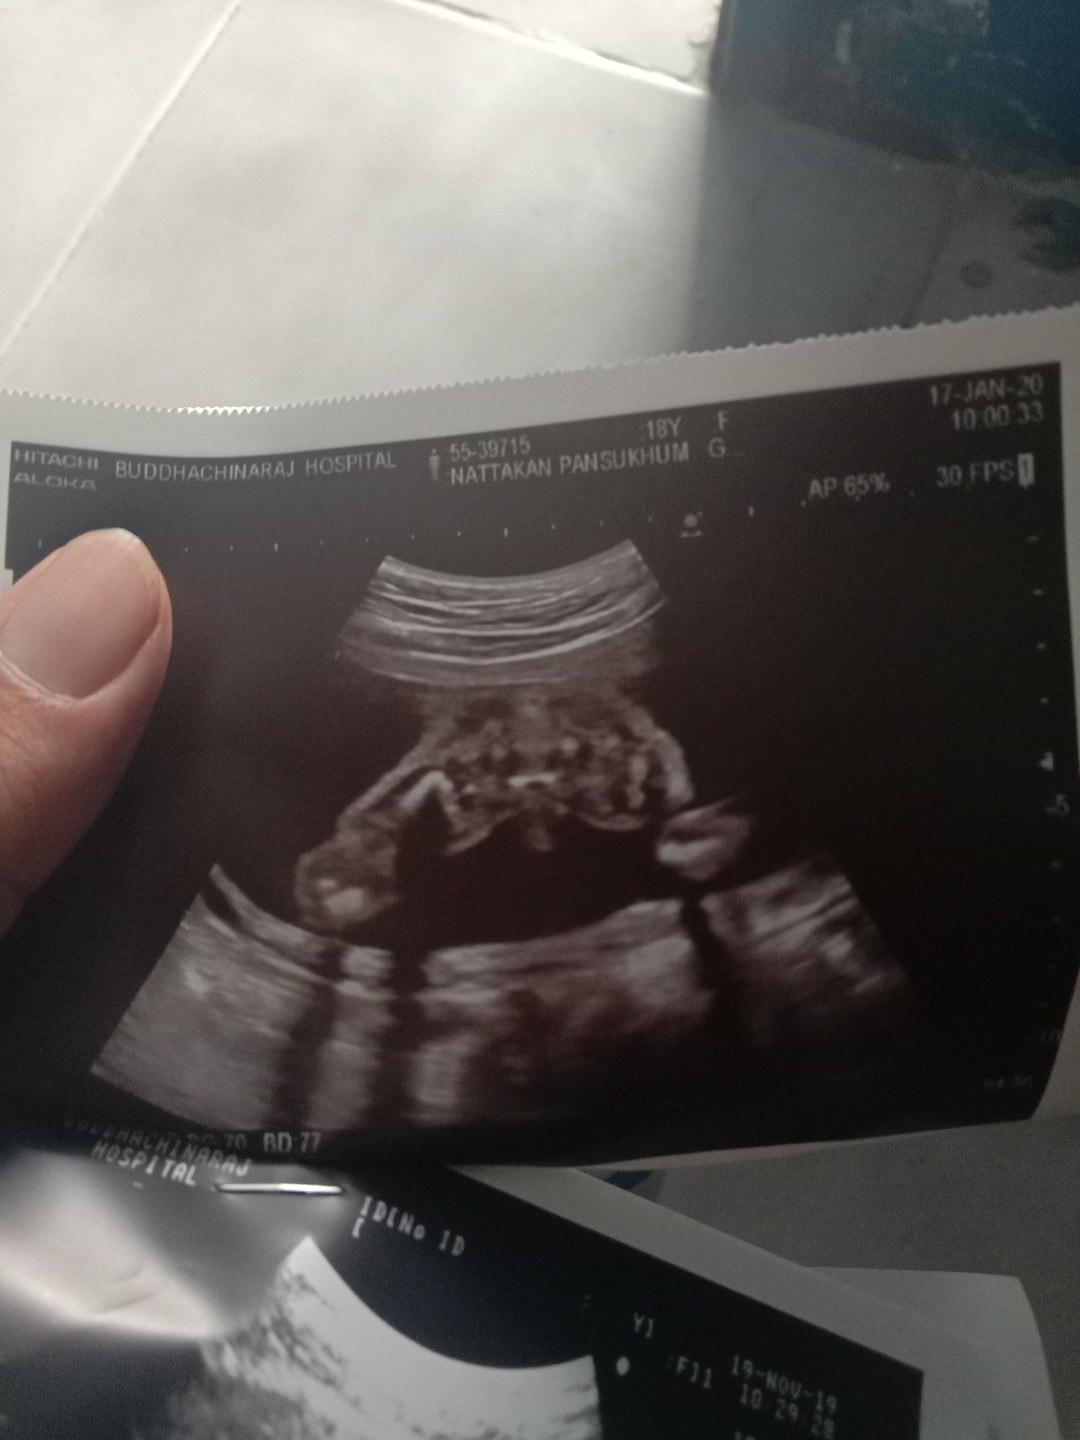

ชายหรือหญิงคะ

แม่ๆว่าเพศชายหรือหญิงคะถ้าซาวออกมาแบบนี้ ถามเพื่อความมั่นใจคะ

เหมือนจะผช.นะคะแม่

น่าจ่ะชายน่ะค่ะ ช้างน้อยแหล่มเลย

ชายแท้แน่นอนค่ะ

เห็นไข่น้อยค่ะ

จู๋โด่ขนาดนั้น

จู๋ชัดมากเลยค่ะ555

ชายจ้า ชัดมาก 555